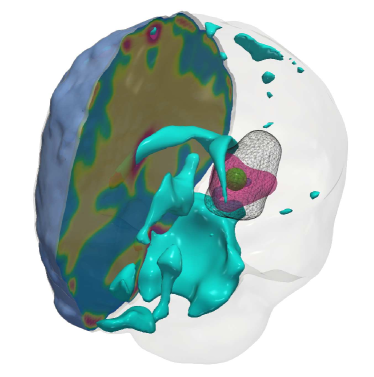

Fig. 4: (a) Description of the visualized brain sub-structures: The figure on the left shows an isometric view of the brain with different tumorous and healthy tissue sub-structures. The figure on the right zooms in on the tumor region and describes each structure. (b, c) Qualitative results for the artificial tumor test-case AT-C1 (a mono-focal, mostly proliferative tumor) with growth parameters ρ=8,κ=0.025formulae-sequencesuperscript𝜌8superscript𝜅0.025\rho^{\star}=8,~{}\kappa^{\star}=0.025. The images show the tumor data (gray wireframe), ground truth tumor initial condition (green volume), reconstructed tumor initial condition (magenta volume), ventricles (cyan volume), and a section of the patient brain geometry. We observe exact reconstruction for smaller tumors with sparsity constraints. The \mathboldL2\mathboldsubscript𝐿2\mathbold{L_{2}} solver fails to obtain the same reconstruction due to its inability to determine the correct reaction coefficient. We refer the reader to Tab. 4 for the quality of final tumor reconstruction.

(a)

Refer to caption

(b) \mathboldL2\mathboldsubscript𝐿2\mathbold{L_{2}}

(c) CS